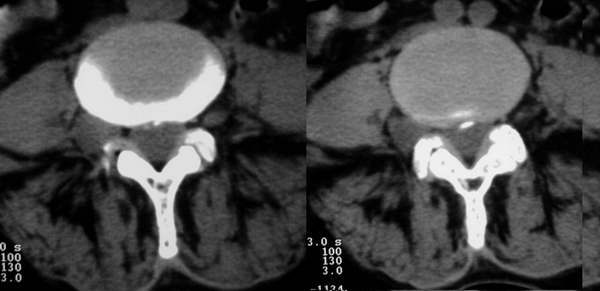

标题: CT3877:神经纤维瘤 [打印本页]

标题: CT3877:神经纤维瘤

女:67岁,右下肢疼痛20余年。

行腰椎间盘扫描。

右侧椎间孔外侧见类圆形软组织肿块边缘清与右神经根关系密切

考虑神经鞘瘤

神经源性肿瘤与束膜囊鉴别,可能以后者可能性大,因为椎间孔未见明显扩大,好象后部有囊性密度,神经源性肿瘤囊变的以神经鞘瘤为多,不过这小的病灶囊变的不多.